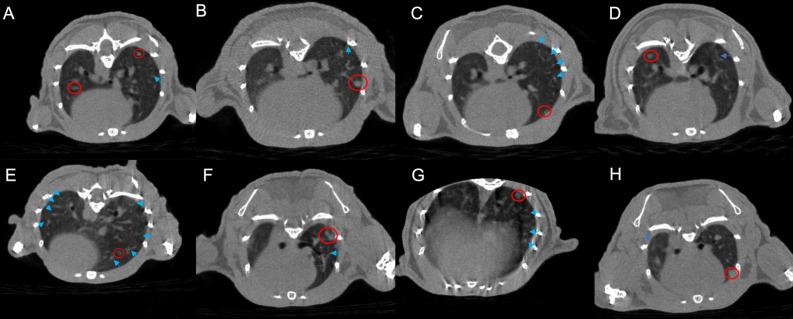

The use of immunotherapy is progressively expanding for the treatment of lung cancer, either alone or in combination with radiotherapy. However, treatment-related adverse events, especially pneumonia, significantly limit the drug's effectiveness in treating lung cancer. The occurrence of lung cancer, immunotherapy, and pulmonary radiotherapy can all contribute to the imbalance in the pulmonary microbiota, rendering the lungs more susceptible to inflammatory reactions. Mouse models of lung transplantation tumor were treated with either PD-1 monoclonal antibody or radiotherapy alone, or in combination. The differences in lung inflammation among the different treatment groups were regularly observed by micro-CT. Further, bronchoalveolar lavage fluid was extracted for macrogenomic and cytokine detection. The transcriptional genome of tumor-filled lung tissue was also sequenced. When treated with a combination of PD-1 and radiotherapy, the CT scans showed more severe pulmonary inflammation. However, with the addition of continuously administered antibiotics, no exacerbation of pneumonia signs was observed. Moreover, the differential gene expression and cytokine profiles in the combination treatment group differed from those in the PD-1 monotherapy group and the radiotherapy monotherapy group. This discrepancy does not seem to be a straightforward superimposition of radiation-induced pneumonia and immune-related pneumonia. Further exploration of changes in pulmonary microbiota revealed specific bacterial interactions with DEGs and cytokines. The underlying causes of this susceptibility are intricate and may be associated with the complexity of pulmonary microbiota imbalance, along with fluctuations in the abundance of specific microbiota species.